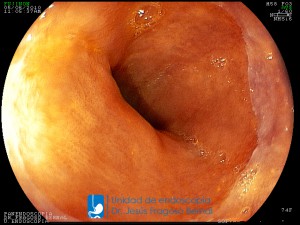

La Unidad de Endoscopía fue creada en 2002 por el Dr. Jesús Fragoso Bernal, es pionera en el estado por la utilización de la tecnología más avanzada, que nos permite ofrecer servicios integrales de diagnóstico y tratamiento para las enfermedades del aparato digestivo.

El profesionalismo de nuestro personal, altamente especializado, se distingue por la calidad y calidez de nuestros servicios con el objetivo de brindar una atención de excelencia en el ambiente más confortable para comodidad y seguridad de nuestros pacientes.

"La Unidad de Endoscopía se ha caracterizado por un progreso continuo desde su inicio marcando la pauta en los procedimientos endoscópicos en el estado de Tlaxcala y estando siempre a la vanguardia tecnológica."

Dr. Jesús Fragoso Bernal